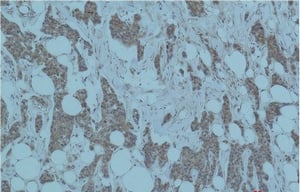

Smad3 Polyclonal Antibody

IHC (Immunohistochemistry), WB (Western Blot)

Synthesized peptide derived from human Smad3 around the non-phosphorylation site of S213.